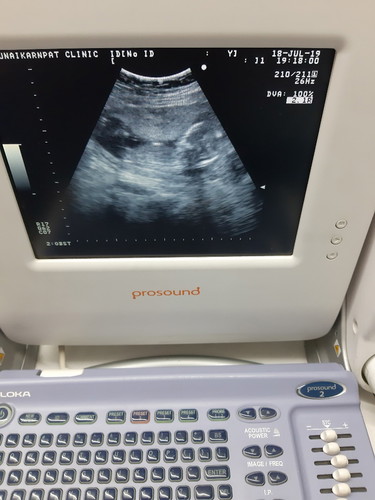

น้ำคร่ำน้อย

วันนี้ หมอนัด 14 w หมอบอกน้ำคร่ำน้อยต้องบำรุง แม่ๆบ้านไหน เป็นบ้าง ค่ะ ขอคำปรึกษาหน่อย ค่ะ ท้องแรก?

ดื่มน้ำเยอะๆ ยิ่งเยอะยิ่งดีวันนึง2-3ลิตรเลยจ้า